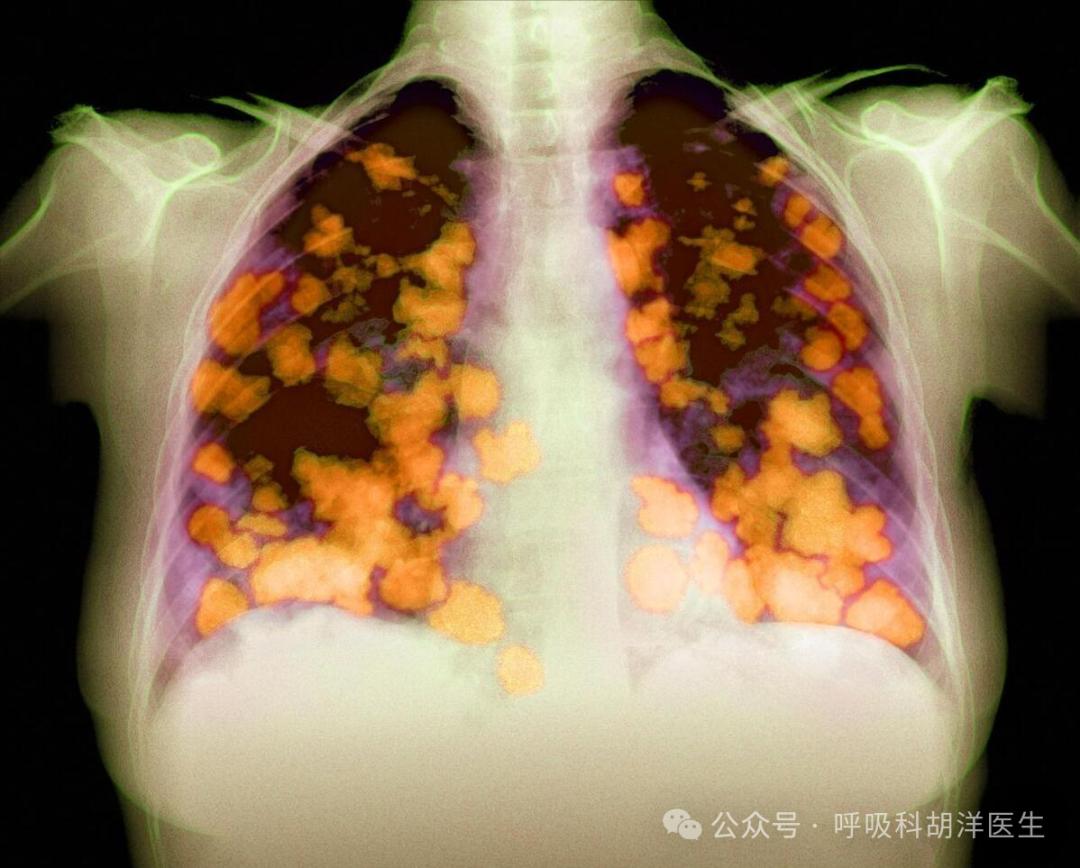

肺癌恶性程度最高,一般期活6-12个月,有哪些治疗进展?

说到恶性程度最高的肺癌,首先想到的一定是小细胞肺癌,与其他三种肺癌完全不同,因此被单独列出。其他三种被称为非小细胞癌,小细胞肺癌在广泛时期的中位生存时间甚至短至6-12个月。即使在定期体检的前提下,也会出现误诊。